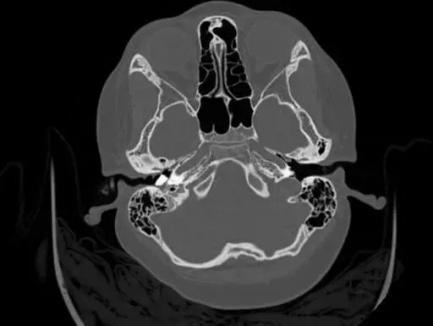

入院后检查右侧外耳道,但因患儿较小,右耳痛明显,不让碰触其右耳,不能明确异物情况。并且患儿入院后4小时突发眩晕,伴反复恶心、多次呕吐,后呕出液伴少量血丝,考虑前庭(主要维持人体平衡)功能损害。急诊CT检查提示右侧外耳道有一大小约6.6mm×4.3mm的异物,已进入鼓室腔。

第二天,耳鼻喉科团队为患儿行急诊手术。在行气管插管全麻后,由副主任医师张金平在旁指导、主治医师谢记发主刀下,通过耳内镜下观察,见外耳道深部一不规则石头,已进入鼓室腔,完全阻塞鼓室内结构,外耳道黏膜部分缺损,外耳道骨质裸露,碰触石头,见缝隙处有少量脓液溢出。

耳内镜下初步对异物情况进行判断,不可能直接取出。遂启动第二方案,微创行耳内切口,扩大术腔,磨除外耳道骨质,扩大外耳道。因石头棱角较多,主刀医生边松动石头边磨除棱角处骨质,小心旋转角度,向外用力终于取出约6.6mm×4.3mm的异物。